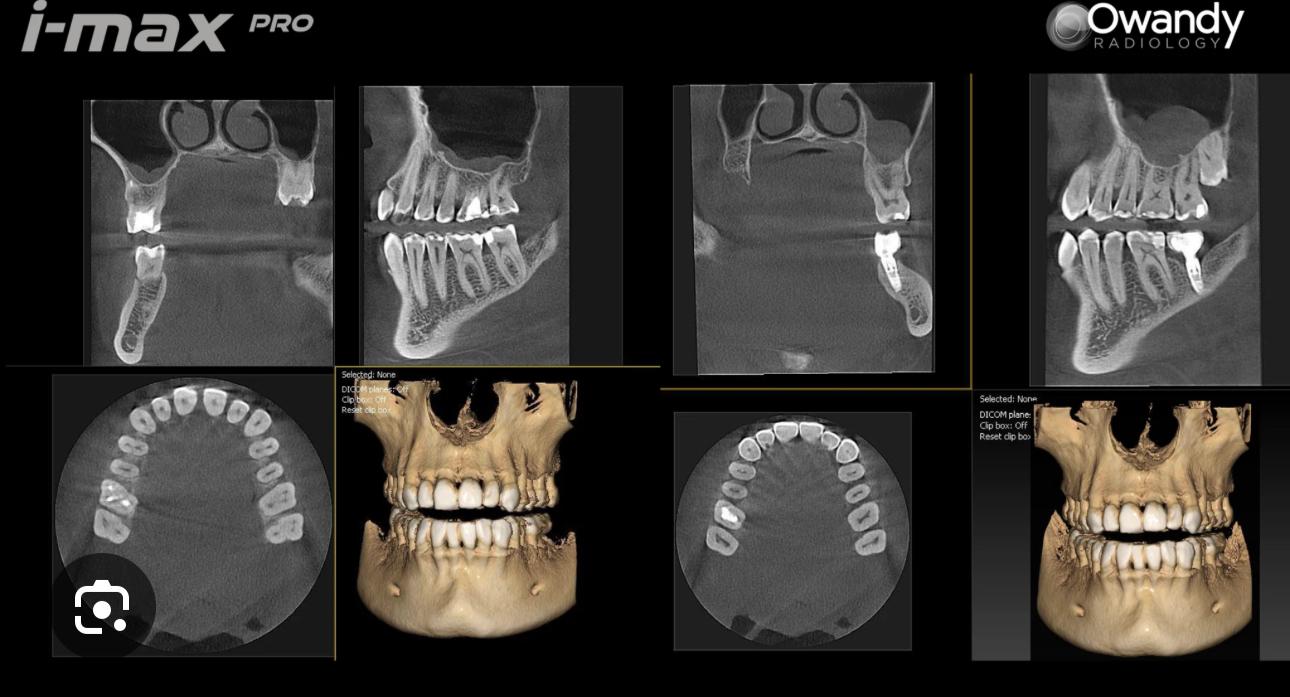

NOVO EQUIPAMENTO DE C.B.C.T., TAC 3D

A clínica de medicina dentária Dr. Ricardo Cruz dispõe de um exame radiológico de elevada precisão, através do novíssimo equipamento de C.B.C.T., TAC 3D, o que permite realizar diagnósticos radiológicos com máximo rigor, através da tecnologia 3D, dando assim mais um importante passo tecnológico na elevada qualidade e segurança que oferece aos seus pacientes, na área da Cirurgia Oral e Implantologia.